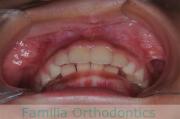

上顎

下顎

前歯の関係など